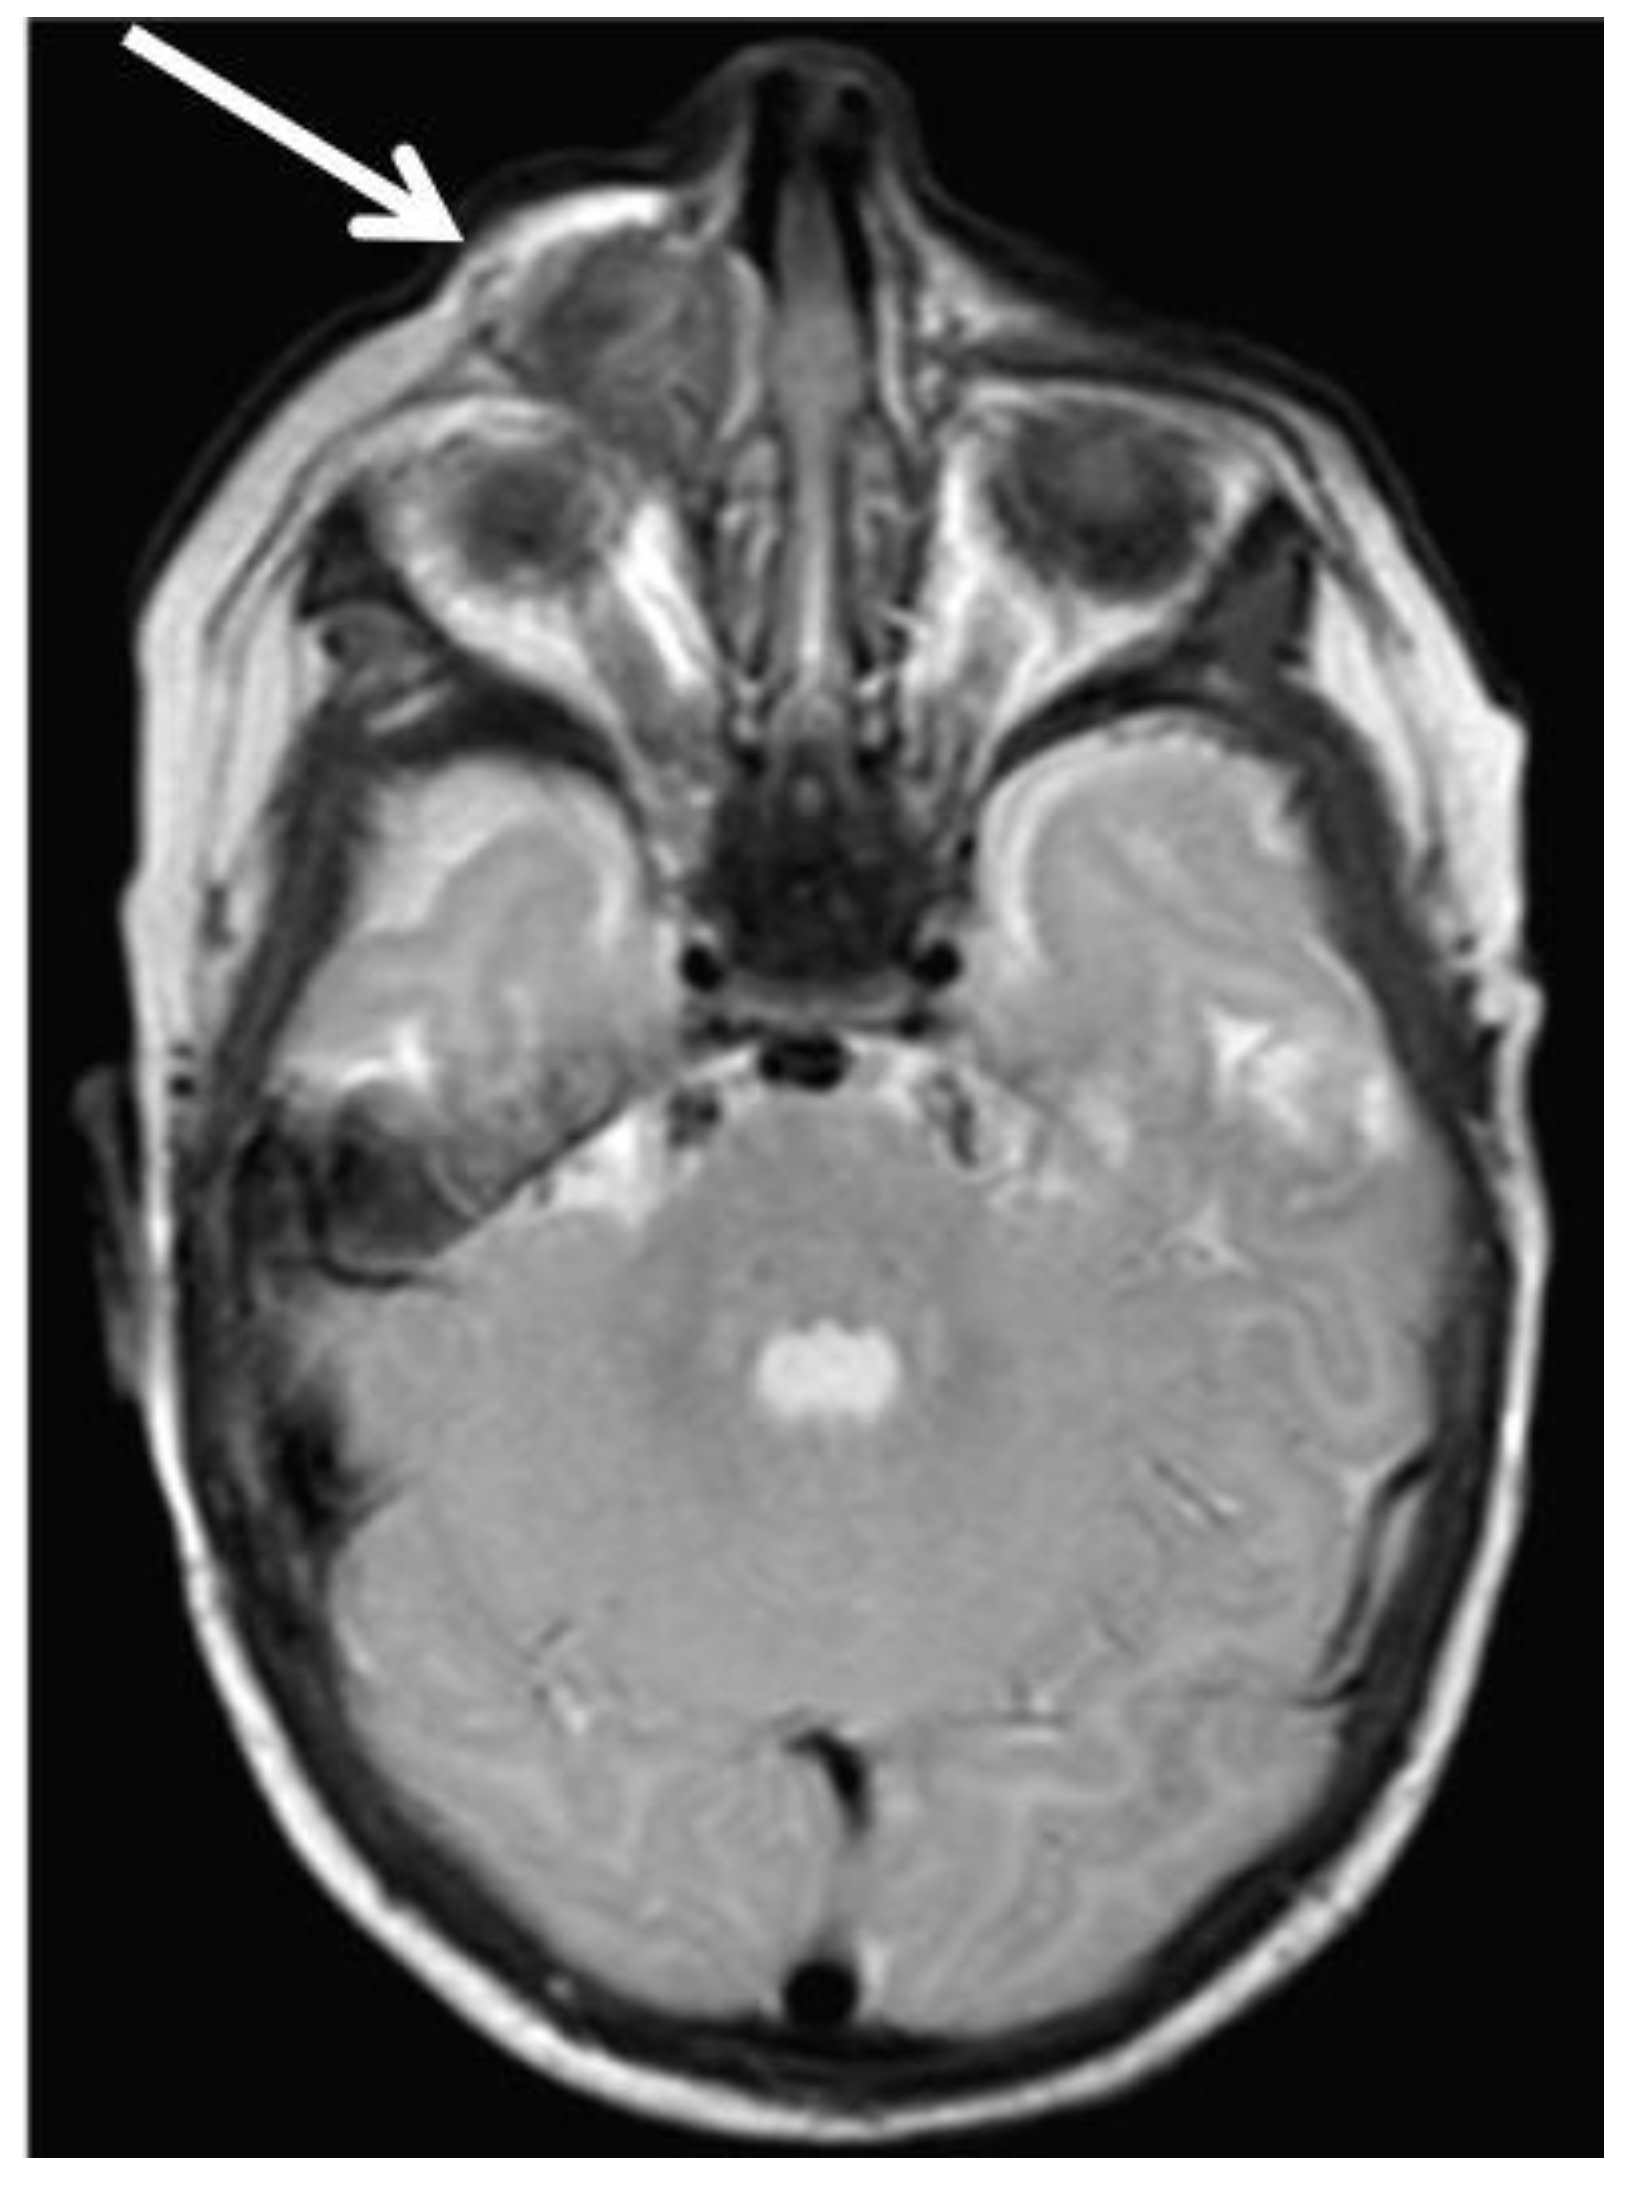

2.1. Patient 1

2.2. Patient 2

2.3. Patient 3

2.4. Patient 4